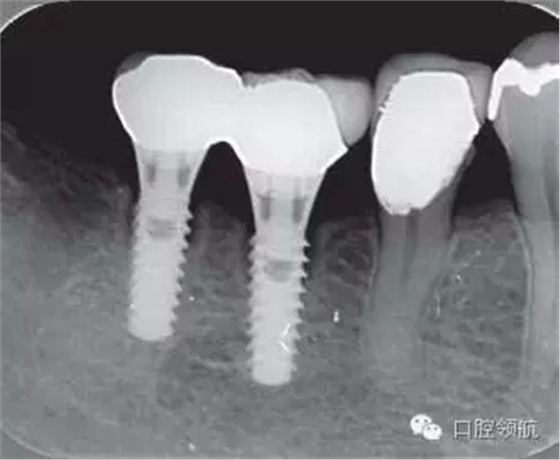

修復體安裝后的2003年1月復診時的X線片上,沒有發(fā)現(xiàn)種植體頸部有骨吸收現(xiàn)象,情況良好(圖2)。但是,2003年8月,因混合陶瓷樹脂部分修復體的破損而進行再制作時,發(fā)現(xiàn)有輕度的咬合疼痛以及舌側(cè)頸部的牙齦有輕壓痛??趦?nèi)沒有觀察到該部位的牙齦紅腫。X線片可以觀察到(左下第6顆牙) 的種植體頸部有達到第4螺紋的骨吸收現(xiàn)象(圖3)。

圖3(左下第6顆牙)的種植體的骨吸收達到第4螺紋(2003年8月)